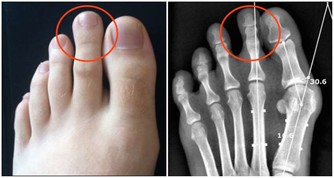

首發症狀常表現為夜間突發第一趾蹠關節疼痛難忍、局部紅腫、皮溫增高,其發病急驟,消退也快,,可在1週左右自行緩解,痛風易反復發作,可累及多個關節,並導致關節畸形。